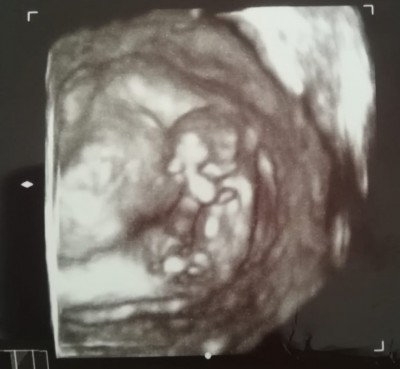

Kızlar 14 haftalık olduk doktora gittim kendini göstermedi ama kız olabilir dedi değişir mi acaba

Gebelik haftası 14.2

Buda bizden olsuun teyzeler 13. Haftaydi erkege benziyor dedi doktorda pek utanga olur bebegim ilk ultrasonda elini yuzune kapatmalar filan :)